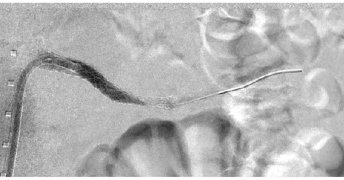

π©»β οΈ Rare trauma complication. This case highlights endovascular repair of a hepatic artery pseudoaneurysm with celiac dissection & intramural hematoma after blunt abdominal trauma, showing the power of minimally invasive management. π https://t.co/F9sOXcp1OU

#VascularTrauma

jvscit.org

Hepatic artery pseudoaneurysm is a concerning yet rare complication of blunt abdominal trauma, with treatment recommended upon diagnosis.1 Endovascular repair of hepatic artery aneurysms has gained...